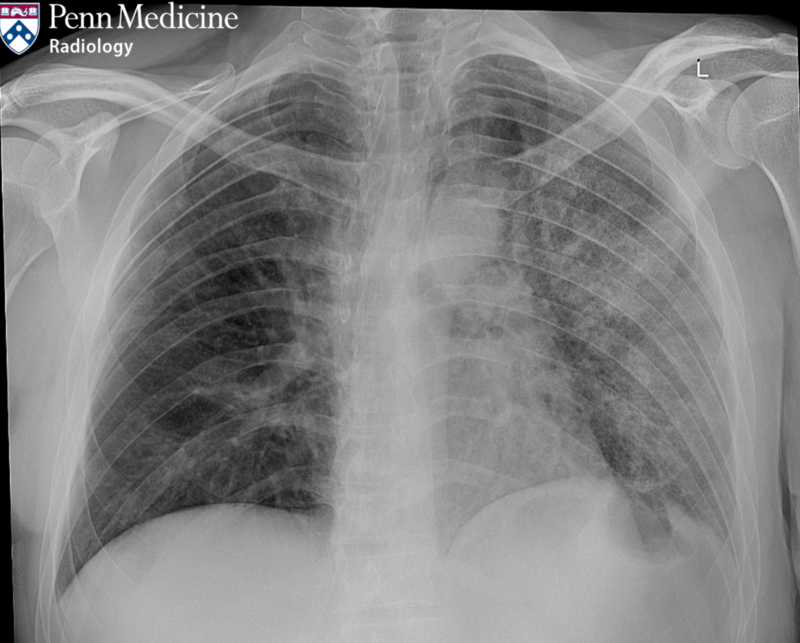

24-year-old man with shortness of breath and unintentional weight loss

A 24-year-old man presented with a three-month history of shortness of breath and unintentional weight loss.

Published Date: February 24, 2026